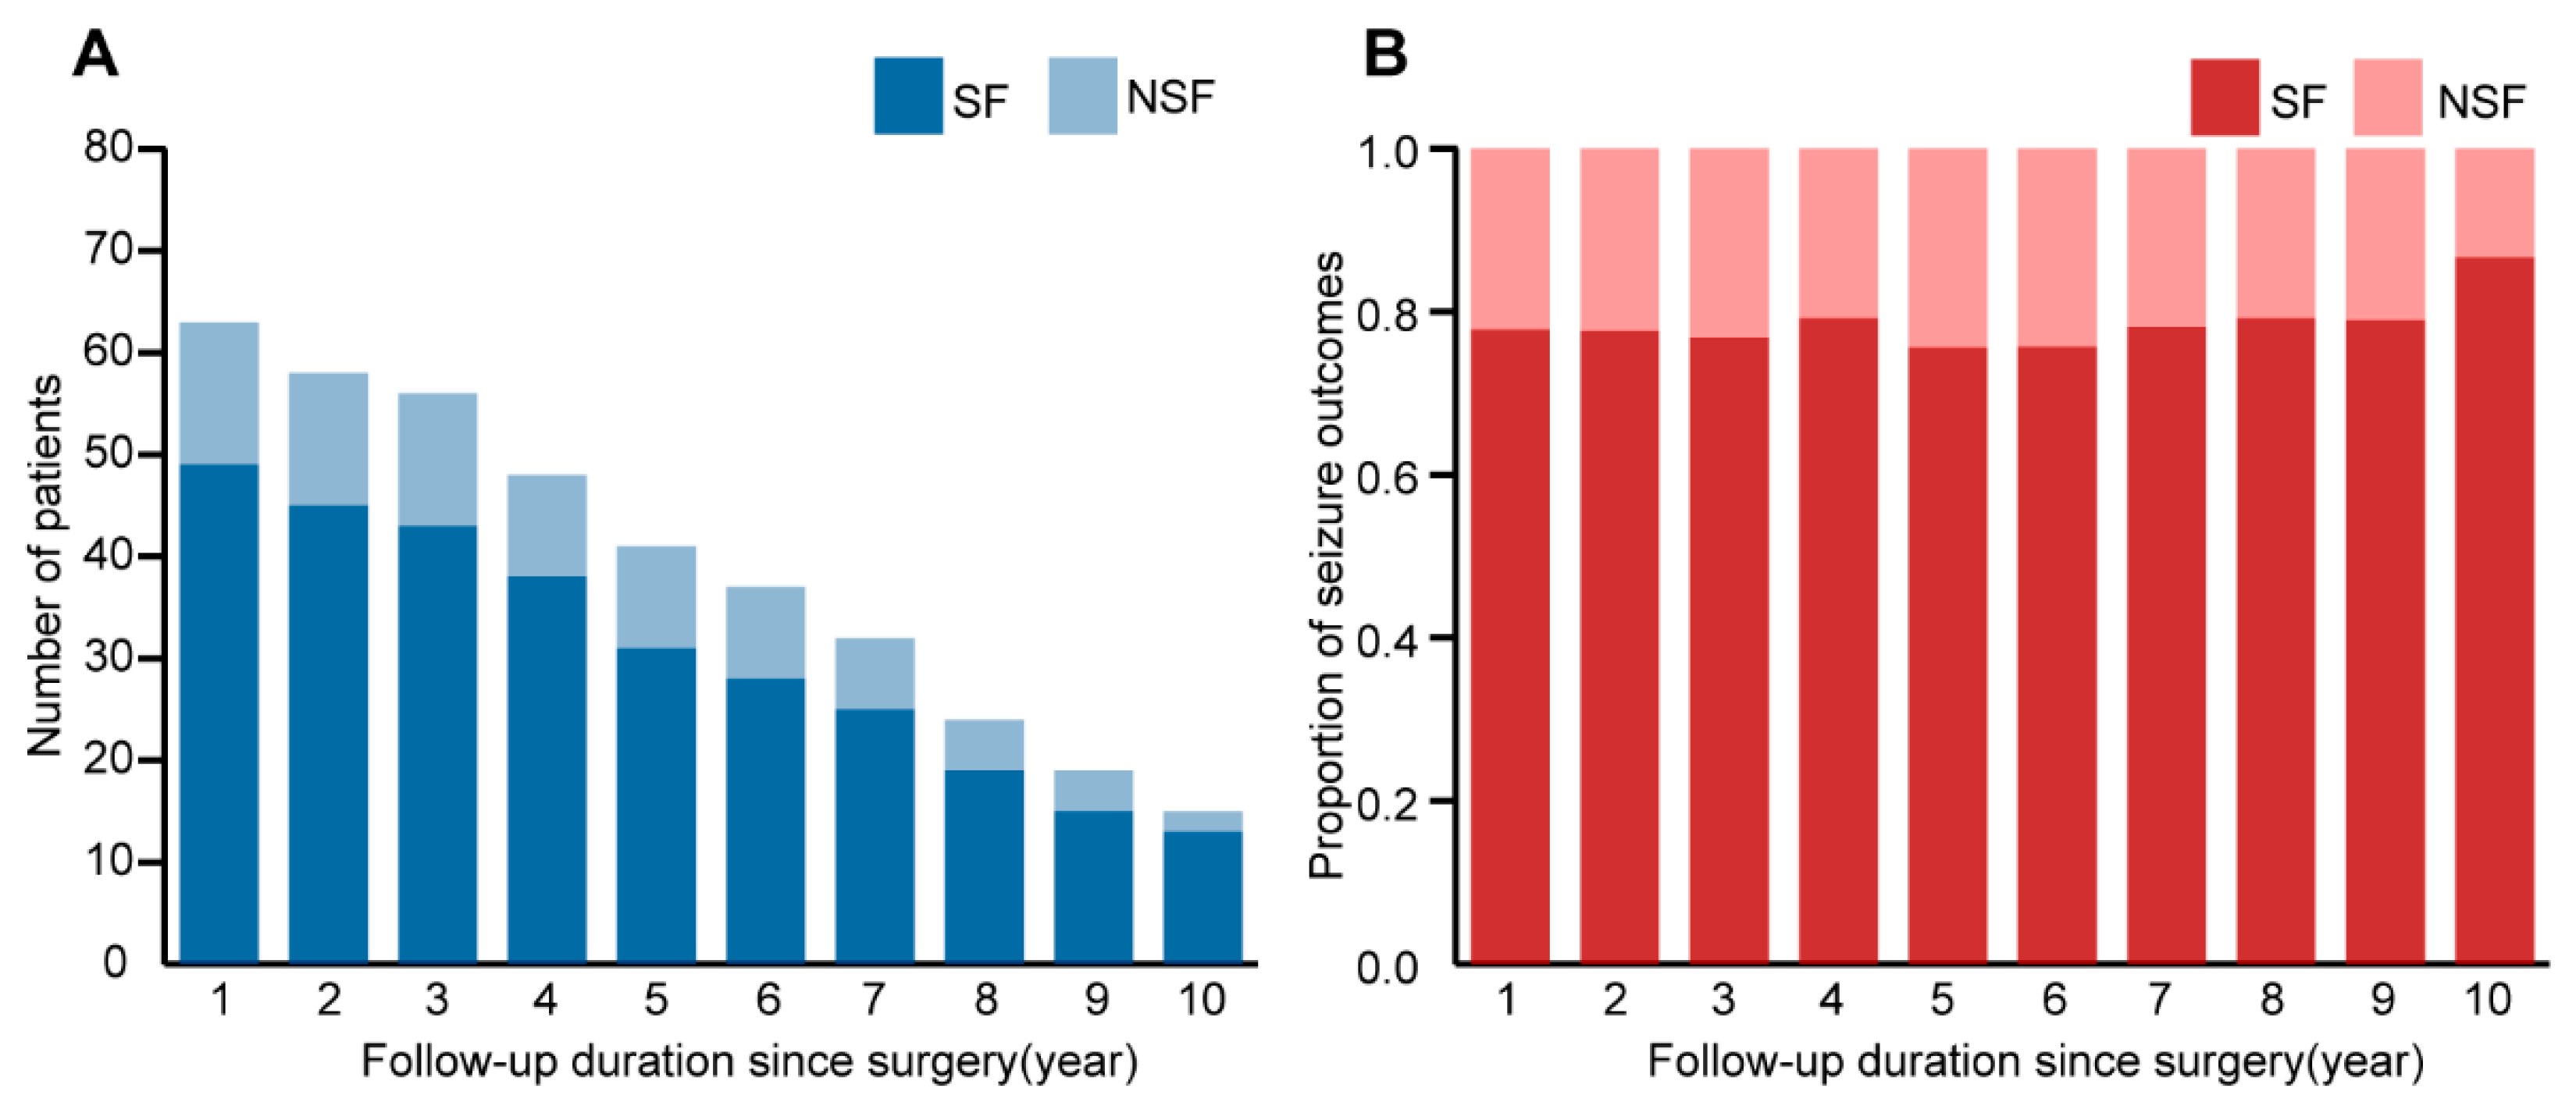

3.4. Follow-Up and Outcomes

3.5. Univariable Survival Analysis